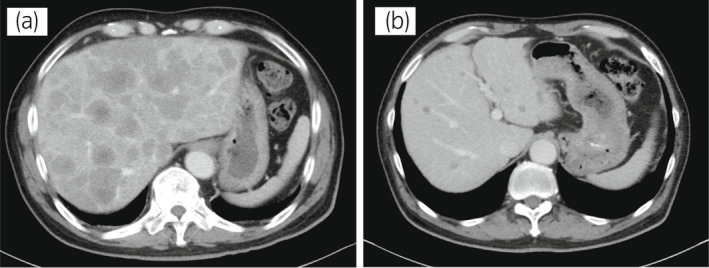

70 歲男性被診斷為轉(zhuǎn)移性 PC,cT3bN1M1b,Gleason 評分(GS)為 4 + 5 = 9,前列腺特異性抗原(PSA)水平為 40.8ng/ml,3 年前伴有胸椎轉(zhuǎn)移。 對前列腺進(jìn)行聯(lián)合雄激素阻斷 (CAB) 治療和質(zhì)子放射治療 (78.0Gy/39fr)。 PSA 水平降至 <0.01ng/ml,CAB 在 2.5 年后停止。 停止 CAB 五個月后,他出現(xiàn)背痛,PSA <0.01 ng/ml。 計算機(jī)斷層掃描 (CT) 掃描檢測到多處肝、骨和淋巴結(jié)轉(zhuǎn)移,神經(jīng)元特異性烯醇化酶 (NSE) 水平高達(dá) 171ng/ml(圖 1a)。 骨轉(zhuǎn)移活檢顯示神經(jīng)內(nèi)分泌前列腺癌 (NEPC) 的診斷(圖 2),患者被轉(zhuǎn)診至佳學(xué)基因合作醫(yī)院。 內(nèi)分泌腫瘤正確治療醫(yī)生用順鉑、依托泊苷和亮丙瑞林治療。 第三個療程后,轉(zhuǎn)移部位明顯縮?。▓D 1b)。 順鉑和依托泊苷治療 1 年,但患者因神經(jīng)病變要求停藥。 他開始服用恩雜魯胺。 治療 3 個月后,患者出現(xiàn)背痛和左鎖骨下淋巴結(jié)腫大(圖 3a)。 肝轉(zhuǎn)移保持不變,順鉑治療后縮小。 通過腫瘤正確用藥850基因檢測證實(shí)了 BRCA2 突變。根據(jù)基因檢測結(jié)果,主治腫瘤科醫(yī)生給予了奧拉帕尼。 三個月后,背痛好轉(zhuǎn),淋巴結(jié)轉(zhuǎn)移縮小,確定為部分緩解(PR)(圖3b)。 肝轉(zhuǎn)移灶保持不變。

圖1:病例1.順鉑和依托泊苷三個療程前后的腹部CT圖像。 (a) 治療前和 (b) 治療后。